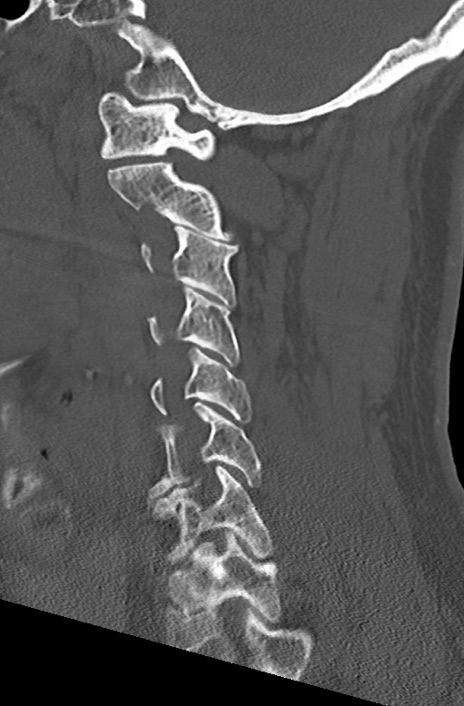

頚椎CT

横断像